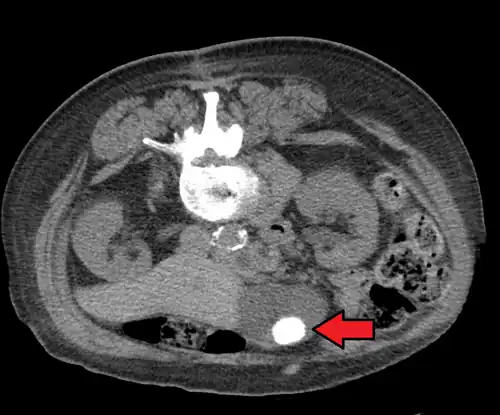

Large gallstones can potentially erode through the gallbladder wall and into the neighboring small intestine. This large stone then travels through the small intestine until it is too narrow for the stone to continue, causing a small bowel obstruction. This obstruction often occurs at previous surgical sites or at the ileocecal valve (the portion of the bowel where the small intestine meets the large intestine). The patient presents with the inability to defecate or pass gas, nausea, vomiting, and severe abdominal pain.[14]

Diagnosis is typically confirmed by abdominal ultrasound. Other imaging techniques used are ERCP and MRCP. Gallstone complications may be detected on blood tests.[2]

On abdominal ultrasound, sinking gallstones usually have posterior acoustic shadowing. In floating gallstones, reverberation echoes (or comet-tail artifact) is seen instead in a clinical condition called adenomyomatosis. Another sign is wall-echo-shadow (WES) triad (or double-arc shadow) which is also characteristic of gallstones.[43]